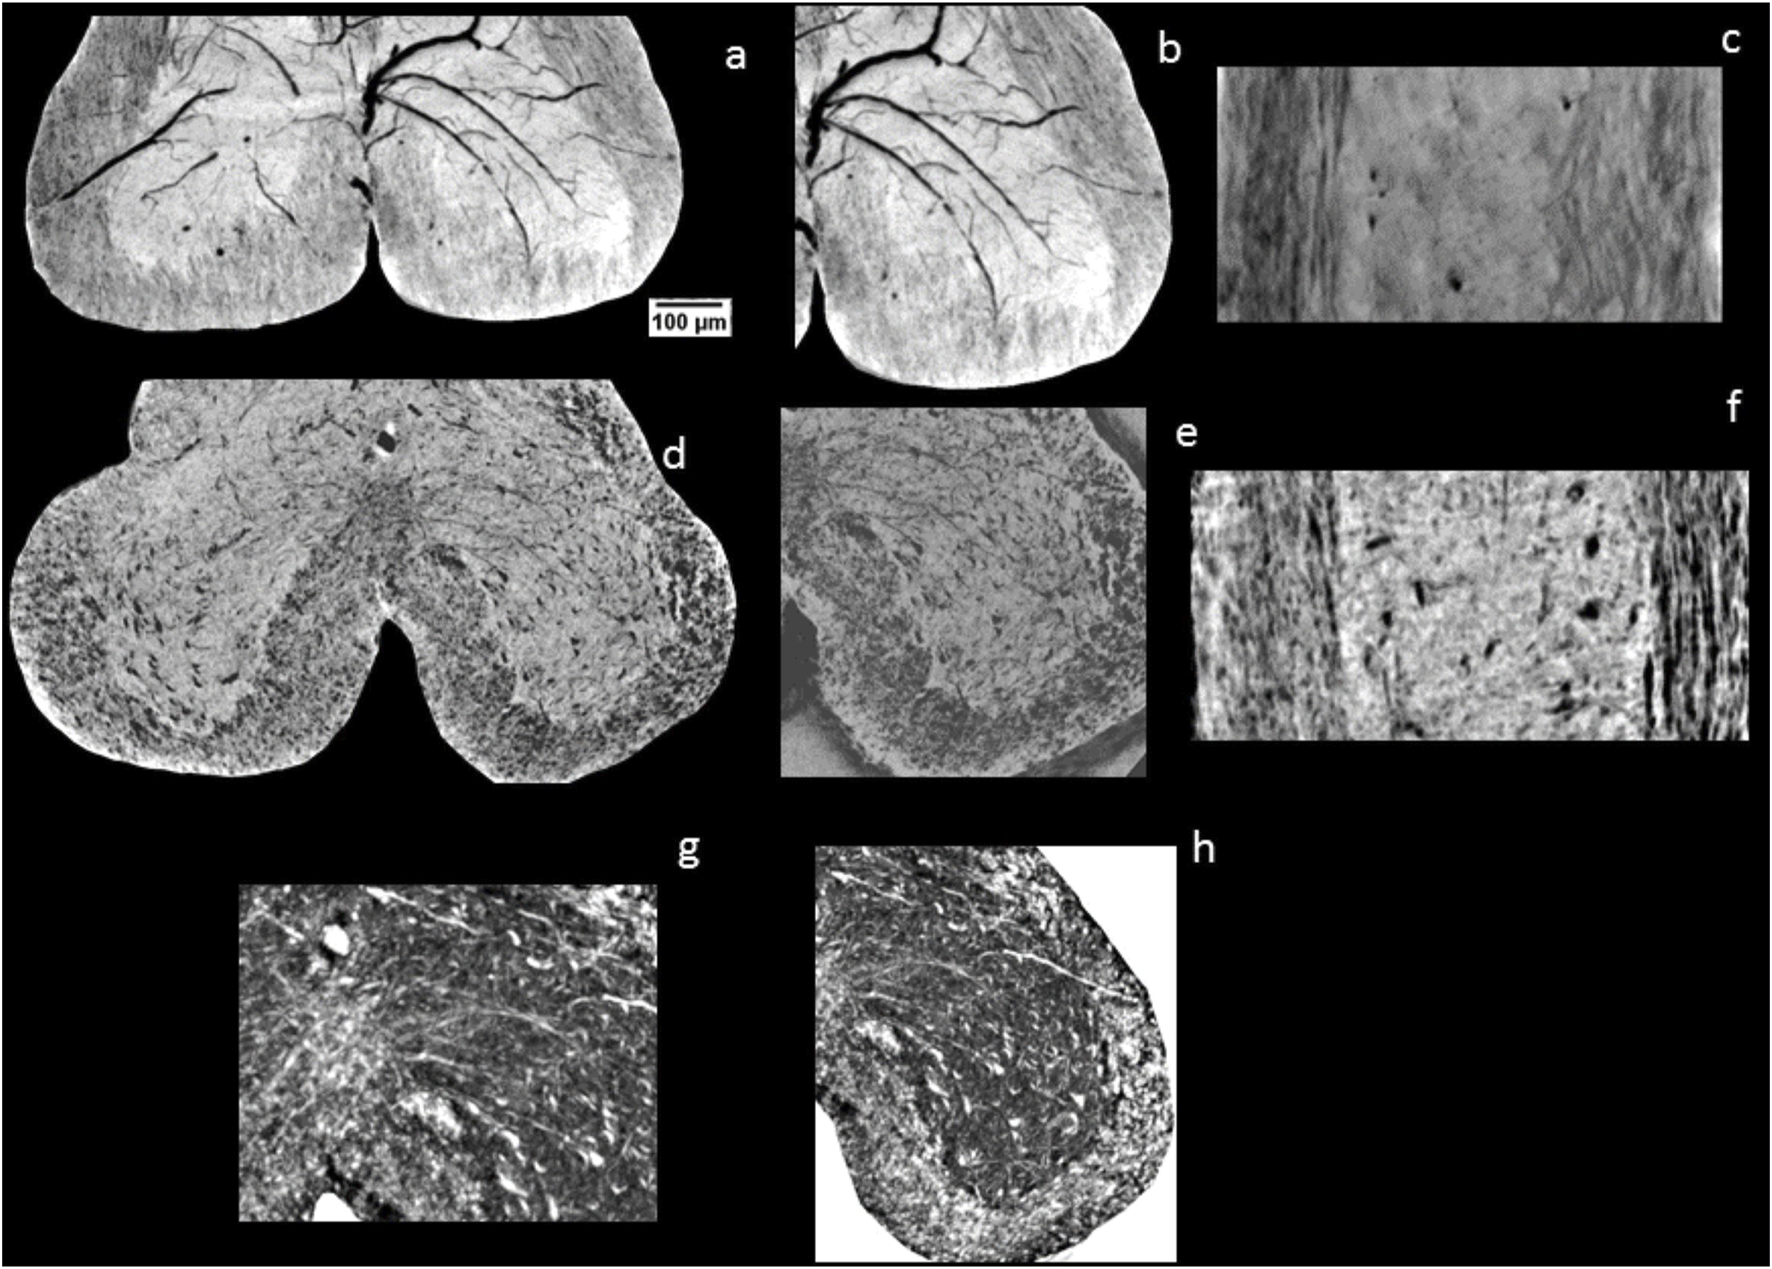

In order to discuss the various features detectable in the tomographic slices with several sample preparations, we report in Figures 1, 2 the XPCT reconstructions of the mouse brain and of the spinal cord (of the same sample) treated with ethanol and with xylene respectively (Figures 1A, 2A-C, 1B, 2D-H).

FIGURE 2

A minimum intensity projection section across 50 μm of spinal cord following ethanol (A–C) and xylene preparation protocols (D–H) respectively. In (A, B) the ventral horn is shown in the axial view. It is observed that in the ethanol preparation, the typical “H” shape of GM is well preserved in contrast, and a different greyscale associated to the phase shift, between WM and GM is noted. While in the sample preparation with xylene there is an enhanced contrast of the border between the GM and the WM. However, the contrast in the GM is too low due probably to the high dehydration that helps to enhance the contrast of the fibers reducing the contrast of the cells in the GM that contain water and lipids. In (C, F) the sagittal view of the spinal cord. (B, E) zoom of the left ventral horn where the vessels and the fibres are segmented respectively. (G, H) segmentation of the ventral white commissure and the nerve fibers in the ventral horn respectively.

We report for each sample the minimum intensity projections across a reconstructed coronal section for the brain in Figure 1 and axial and sagittal cross section for the spinal cord in Figure 2 [31]. A general inspection reveals as Xylene based sample preparation significantly enhances the contrast of the WM by effectively removing water and lipids from the tissue, which leads to a clearer delineation of the protein matrix against the surrounding air. This preparation technique generates a novel contrast without the need for additional staining or embedding procedures. As a result, the contrast between the WM and surrounding tissues is markedly improved, allowing for better visualisation of axon fibres such as in the brain region around the hippocampus including the corpus callosum (cc) and the fibres forming the thalamus nuclei. Specifically, according to the mouse brain Atlas the dorsal fornix (df) and the cingulum bundle (cb) can be identified.

In addition, the anterior or ventral white commissure, a collection of nerve fibres that cross the midline of the spinal cord and transmit information from or to the contralateral side of the brain, is visible [1, 31].

These crossing fibres make the anterior white commissure an important link in communication between the brain and the contralateral side of the body for both sensory and motor pathways.

On the other hand, the ethanol perfusion significantly enhances tissue rigidity, preventing the collapse of vessel walls [23]. This results in high-contrast images that clearly depict the morphology of vascular structures, making ethanol perfusion particularly effective for visualising brain and spinal cord vascularization (see Figures 1A, 2A). The vascular networks that supply blood to the spinal cord become distinctly visible without the need for a contrast agent.

We evaluate the efficiency of different sample preparation methods by calculating the gain, defined as the ratio between the contrast-to-background ratio (CBR) in xylene- and ethanol-perfused samples (for CBR, see. e.g., [38], Supplementary Materials and Supplementary Figure S1) CBR xylene/CBR ethanol. The same component and the same region were considered in both sample preparation for the quantification (see Supplementary Figure S1). We observe a gain of 18,1 in the brain, on the other hand in the spinal cord we estimate a gain of 0.5 probably due to the small cross section of the spinal cord and the important effect of the shrinkage due to the sample preparation. However, there is a contrast increase of the fibers as a consequence of the sample preparation with xylen.